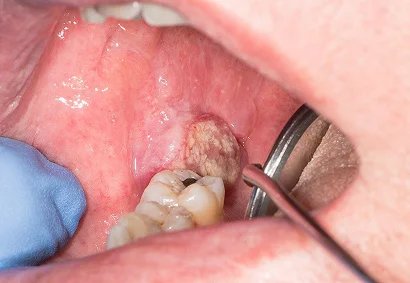

Very advanced oral cancer often involves deep tissues of the mouth, jaw, or face, making treatment more complex. At this stage, patients may experience difficulty in eating, speaking, and even breathing. But with modern medical and surgical advancements, meaningful recovery is still possible. At Faith Hospital, treatment focuses on complete cancer control along with functional and aesthetic reconstruction. Each patient receives an individualized plan — combining advanced surgery, reconstruction, and rehabilitation — to help them return to normal life with dignity and confidence.